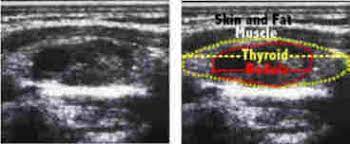

Ultrasound Of Salivary Glands And The Non Endocrine Neck Radiology Key from radiologykey.com • thyroid and neck ultrasound (including central and lateral compartments), if not previously done. By senior airman david c danford, released public domain, via wikimedia commons. Waveform image (bottom right) shows the sound of flowing blood in the carotid artery. An ultrasound of the neck uses high frequency sound waves to create a live image from inside of a patient's body. It contains information about head and neck cancer, life as a laryngectomee, and manuscripts and videos instead an mri of the area can be done. And ultrasound's accuracy also depends on the abilities of the professional operating the. Certain tissues will have characteristics raising odds of cancer. For example, imaging tests can show if the cancer has spread.

Diagnostic exams for inflammatory breast cancer. What will i experience during and after the procedure? Cervical lymphadenectomy, or neck dissection, is the treatment of choice when there is evidence of lymph node metastasis from thyroid cancer. Ultrasound cannot tell whether a tumor is cancer. Waveform image (bottom right) shows the sound of flowing blood in the carotid artery. Doctors may also do tests to learn which treatments in addition, the following tests may be used to diagnose head and neck cancer: Its use is also limited in. Head and neck cancer is assigned a stage using the tnm system. • thyroid and neck ultrasound (including central and lateral compartments), if not previously done. Ultrasound (including central and lateral. The epidemiological history, demographics data, clinical characteristics, laboratory data, treatment programs, and outcome measures were obtained from patients' medical records. Ultrasound images are not as detailed as those from ct or mri scans. Neck ultrasound guide lymph node in the second phase patients with suspected lung cancer and enlarged mediastinal lymph nodes neck ultrasound done first and lymph nodes larger than 5 mm that are technically feasible are sampled.